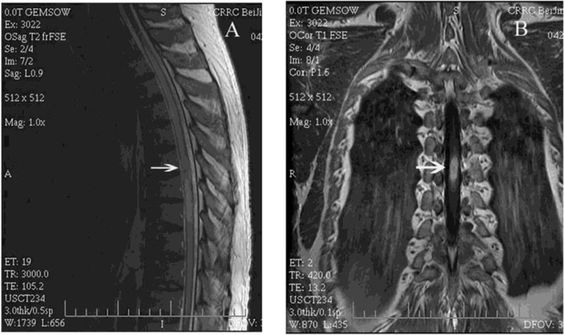

Что показывает МР-томография грудной части позвоночного столба?

Существует официальный перечень показаний, на основе которых делают МРТ грудного позвоночника:

- Выявление причины ущемления нервного корешка;

- Сильный болевой синдром после травмы позвоночника;

- Инфекционные заболевания с поражением спинного мозга;

- Выявление очагов разрушения оболочки нерва (демиелинизация);

- Недостаточность кровоснабжения исследуемой области;

- Генетические аномалии сосудов, мягких тканей.

На практике МР-сканирование используется гораздо шире. Большим «бонусом» будет, если врачи лучевой диагностики выявят сужение позвоночного канала, остеопороз (снижение плотности кости), деструктивные поражения, расслоение стенки грудной аорты.

Инновации МРТ грудного отдела

Для обследования позвоночника применяются не только взвешенные томограммы (T1 и T2). Разработан целый комплекс методов, чтобы сделать мрт грудного отдела позвоночника более качественным – перфузия, функциональная МРТ, трактография, тензорная диффузия, МР-спектроскопия. Врачи-рентгенологи знакомы с данными способами диагностики и могут посоветовать их применение при необходимости.